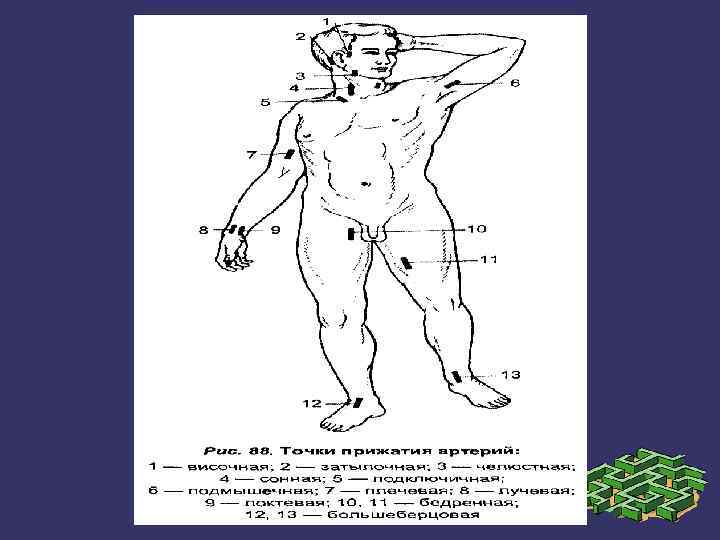

Кейбір қан тамырлардың жарақаттануы кезінде қанды тоқтату үшін ірі қан тамырларды сүйекке саусақпен басу қолданылады.

Самай артериясы

Ұйқы артериясы

Бұғана асты артериясы

Қолтық артериясы

Иық артериясы

Сан артериясы